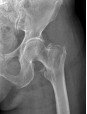

4月23日,贵州航天医院第58次晨读会由我院骨科副主任医师张艳金作学术交流,他以“加速康复指导下的快速手术”为题,详细讲解了老年股骨粗隆间骨折与儿童四肢骨折的临床诊疗难点,结合加速康复外科(ERAS)核心理念,重点阐述了ERAS理念在两大人群中的创新实践,实现患者入院后6至24小时内即可接受手术治疗。针对老年髋部骨折患者,提出通过多学科协作(MDT)与微创手术优化围术期管理,在确保安全前提下缩短术前等待时间,实施精准化麻醉及术后康复方案,可有效降低并发症发生率、改善患者生活质量和预后效果。在儿童骨折领域,强调微创术式与心理干预并行的双轨策略,既减少手术创伤对骨骼发育的影响,同时关注患儿心理疏导,实现生理功能与心理健康同步康复。并通过典型案例的影像学资料与随访数据,直观展示了ERAS理念指导下骨科治疗模式的创新成果。 贵州航天医院骨科 专家简介 赵学平 中共党员,骨科党支部书记、主任,主任医师 临床擅长:从事骨科临床工作30余年,对骨科常见疾病的诊治具有丰富的临床经验。 世界中医药联合会脊柱康复专业委员会常务理事,中华中医药学会整脊分会常务委员,中国中西医结合学会骨伤科分会肢体矫形功能重建与康复专家委员会常务委员,中国研究性医院学会骨科创新与转换专业委员会关节外科学组保髋工作委员会常委,中国康复技术转化及发展促进会骨外科与康复技术转化专业委员会常务委员,泛珠三角区域运动医学联盟(PPRD-SMA)理事会常务理事,中国研究型医院学会运动医学专业委员会委员,贵州省中医药学会整脊分会副主任委员,贵州省中西医结合学会银质针专业委员会副主任委员,贵州省康复医学会骨与关节专业委员会常务委员,贵州省人民医院骨科专科联盟常务理事,贵州省康复医学会骨内科专业委员会常务委员,中华医学会贵州省骨科学会委员,贵州省康复医学会脊柱脊髓专业委员会常务委员,贵州省运动医学分会委员,贵州省康复医学会骨与软组织肿瘤专业委员会委员,遵义市医学会创伤分会副主任委员,贵州省康复医学会骨内科专业委员会遵义地区分会常务委员,遵义市医疗事故鉴定、伤残鉴定、工伤鉴定、司法鉴定专家。 长期从事骨科临床研究及教学工作,在国家级、省部级杂志发表论文20余篇,SCI论文2篇,参与主编骨科专著2部,主持省部级科研项目2项,参与指导省部级、市级科研项目6项。 陈明勇 骨科副主任,副主任医师 临床擅长:从事创伤骨科工作约20年,对骨缺损、骨不连、骨肿瘤、肢体畸形等的肢体矫形重建及功能重建,慢性化脓性骨髓炎的根治治疗、糖尿病足的保肢治疗、快速康复理念(ERAS)下的老年骨折的诊治,四肢复杂骨折的诊治,四肢骨折等微创手术治疗具有丰富的临床经验。 2004年毕业于遵义医学院临床专业,曾在中国人民解放军总医院、广西医科大学第一附属医院、上海第六人民医院骨科进修。中国中西医结合学会骨伤科专业委员会横向骨搬移治疗糖尿病足及微血管网再生学组首届委员,遵义市医学会创伤分会常务委员。 瞿 辉 中共党员,骨科副主任医师 临床擅长:对骨科的常见病、关节外科、脊柱外科及运动医学疾病的诊治具有丰富的临床经验,熟练掌握骨科手术操作技术。 毕业于遵义医学院临床医学系,2005年前往广州中山大学第一附院骨显微医学部进修学习,2011年前往成都华西医院进修学习,并多次在省内外学习骨科相关知识,是中华医学会骨科分会会员。 赵兴东 骨科主任医师 临床擅长:擅长骨科的常见病及各种创伤、四肢骨折创伤修复、骨感染、手足疾病的诊治和手足体表畸形的矫形整复,熟练掌握骨科四肢骨病及创伤的手术操作技术,尤其在四肢关节复杂性损伤、手足外伤、组织缺损创面、难治创面的皮瓣修复方面及平足、高弓足矫形方面及四肢慢性疼痛诊治、康复方面具有丰富的临床经验。 硕士研究生,毕业于遵义医学院临床外科系,2015年前往山东省立医院手足外科进修学习;遵义市医学分会创伤分会第一、二届委员,遵义市手外科医学会第二委届员会常务委员;在省级及省级以上期刊发表文章9篇,参编著作2部,参与主持并完成市级课题1项,参与市级课题2项、省级课题1项。 张艳金 中共党员,骨科副主任医师 临床擅长:从事骨外科工作16年,对复合伤、多发伤的救治、四肢骨干骨折、关节周围骨折、骨肿瘤、骨髓炎等诊治具有丰富的临床经验。 中共党员,硕士研究生,2006年本科毕业于山西医科大学第二临床医学院,2011年研究生毕业于北京军区总医院;在“老年COPD患者合并髋部骨折的诊治”国际合作课题组研究两年,在老年髋部骨折的诊治方面具有丰富的经验,并发表论文6篇;主持遵义市级课题1项,承担遵义医科大学的临床教学工作,获得遵义医科大学优秀带教老师荣誉。编撰有《骨科疾病诊疗精粹》一书,开展2项新技术,编撰地方规范《务川自治县创伤骨科常见疾病诊疗规范》一书。 张俊凯 骨科副主任医师 临床擅长:从事骨科临床工作28年,对创伤骨折、骨感染、骨缺损、骨不连等外科诊治,四肢骨折的微创手术治疗,四肢复杂骨折(如关节内粉碎性骨折、多发骨折等)的损伤控制及手术治疗等具有丰富的临床经验。 1995年毕业于遵义医学院临床专业,2009年前往复旦大学附属医院骨科进修1年。 卢懿明 中共党员,骨科副主任医师 临床擅长:从事骨科工作18年,对创伤骨折、四肢骨折的微创手术治疗、四肢复杂骨折(如关节内粉碎性骨折、多发骨折等)的损伤控制及手术治疗,尤其是髋部骨折的PFNA等微创技术,踝关节骨折、膝关节周围骨折的Mipo微创技术等具有丰富的临床经验,开展了4项新技术,发明6项新型专利技术。 2005年毕业于遵义医学院临床专业,2017年,前往南方医科大学第三附属医院骨科进修半年,回院后运用Mipo技术对骨干骨折及干骺端骨折的治疗技术,同时积极开展骨盆骨折、髋臼骨折腹直肌外侧切口的应用;发表了多篇专业论文,经常参与省内外学术交流会授课,获得医院荣誉称号多个。 邬夏荣 骨科副主任医师 临床擅长:从事骨科工作16年,对四肢复杂骨折、骨肿瘤的诊治,尤其是足踝创伤、慢性踝关节损伤、平足症等诊疗具有丰富的临床经验。 2006年毕业于遵义医科大学临床医学专业,曾在陆军军医大学西南医院进修学习,发表多篇骨科学术论文。 余德怀 中共党员,骨科副主任医师 临床擅长:从事骨科工作10余年,对运动医学、骨关节、脊柱外科常见病、多发病的诊治具有丰富的临床经验。 硕士研究生,2011年毕业于遵义医学院临床医学专业,曾前往遵义医科大学附属医院运动医学专业进修学习;是贵州省医学会运动医学分会青年委员,西部关节镜联盟委员;发表多篇骨科学术论文。 冯 乾 骨科副主任医师 临床擅长:从事骨科工作近20年,熟练掌握骨科多发病及常见病的诊治,尤其对脊柱退变性疾病的诊断及治疗具有丰富的临床经验,主要研究脊柱微创相关治疗方式,能熟练开展椎间孔镜及UBE。 曾前往北京大学第三医院进修学习疼痛及椎间孔镜、首都医科大学友谊医院专业进修脊柱内镜;是贵州省康复医学会第三届脊柱脊髓专业委员会委员;发明专利3项、发表脊柱外科专业论文多篇。 赵小锋 中共党员,骨科副主任医师 临床擅长:从事骨科临床工作11年,对骨科常见病、多发病诊疗有较为丰富的临床经验,擅长脊柱相关疾病诊断及治疗,尤其是颈、腰、腿疼痛疾病诊断及治疗,擅长胸腰椎骨折微创经皮穿刺内固定术、经皮穿刺椎体成形术、经皮穿刺脊柱内镜下腰椎间盘摘除术、单纯开创腰椎间盘摘除术、腰椎滑脱复位椎间植骨椎融合内固定术、腰椎管狭窄减压融合内固定术及人工髋、膝关节置换术等。 2012年毕业于遵义医学院外科学专业硕士研究生,2019年参加“遵义市115医学人才精英计划”于上海交通大学第一附属医院培训学习,2023年于北京大学第三人民医院脊柱外科进修学习,曾获得遵义市优秀医师荣誉称号。 遵义市手外科第一届委员,遵义市医学会创伤分会第一届委员,遵义市医学会创伤分会第二届委员,贵州省康复医学会第三届脊柱脊髓专业会委员,遵义市医学会烧伤与整形外科学分会委员,发表论文5篇,其中国家级核心期刊1篇,SCI论文1篇,主持市级课题1项并结题,参与市级课题2项。 贵州航天医院骨科 简介 基本情况 贵州航天医院骨科组建于20世纪60年代,前身是以创伤和断肢(断指)再植闻名于世的上海市第六人民医院骨科,中国断肢(断指)再植的奠基者、中科院院士陈仲伟等著名专家、学者多次莅临科室指导医疗、教学,是贵州省最早拥有专业骨科技术科室之一,在70年代开展了贵州省首例断肢(断指)再植手术。组建50余年来,诊治患者已逾百万,挽救了无数的伤病员,成为了保障遵义地区人民群众健康的重要支撑。 经过几代人的不懈努力,今天的骨科,已由创伤骨科发展至骨病、骨肿瘤、骨结核等领域,现有脊柱外科、关节外科、四肢创伤、手足外科四个亚专科,成为了集医疗、教学、科研于一体的综合学科,是贵州省临床重点专科、遵义市临床重点专科、遵义市骨科临床医学中心、遵义市基层骨科专科联盟理事长单位。 科室目前开放床位110张,共有医护人员50余人,副高级以上专家18人,硕士研究生15人。拥有一流骨科医疗设备多台,每年不定期选派优秀技术骨干到全国各大知名医学院校进修、学习、参观、交流,并邀请国内、国外知名专家教授来院进行交流、指导,通过不断引进国内外先进的诊疗技术,科室医疗技术水平稳步提升,为广大人民群众提供了优质的医疗服务。 专科特色 骨一科 (一)骨缺损、骨不连的肢体与功能重建 胫骨横向骨搬移技术治疗糖尿病足: (二)慢性骨髓炎的根治治疗 (三)肢体缺血性疾病如糖尿病足、脉管炎的保肢治疗 (四)皮瓣修复 (五)复杂创伤的治疗 (六)老年髋部骨折及小儿骨折快速手术 老年髋部骨折: 骨二科 (一)胸腰椎骨折微创经皮椎弓根螺钉固定术 (二)老年性骨质疏松性患者腰椎滑脱脊柱内固定术(骨水泥螺钉) (三)V形双通道脊柱内镜技术(VBE)腰椎融合术治疗腰椎退行性疾病 (四)老年性骨质疏松性骨折(PVP/PKP)术 (五)人工髋关节置换术 (六)双侧股骨头坏死人工全髋关节置换 (七)右侧全髋置换术后假体周围骨折翻修 (八)人工膝关节置换术 (九)人工膝关节假体松动翻修 (十)关节镜技术 传统手术切口 关节镜技术切口 诊疗范围 骨一科 1.四肢创伤、矫形。 2.手、足踝外科。 骨二科 end